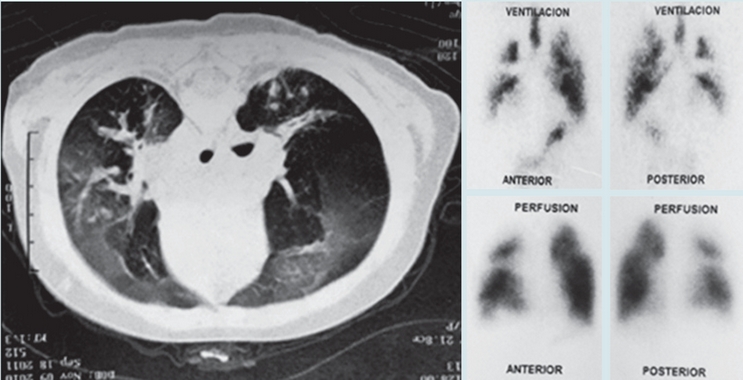

En las Figuras 1 y 2 se observan imágenes diagnósticas de algunos de nuestros pacientes y en la Figura 3 la evolución favorable de la tomografía (en un caso) después de varios años de seguimiento. En nueve casos se realizó exploración funcional respiratoria encontrando obstrucción significativa de la vía aérea en seis, obstrucción leve en dos y ausencia de obstrucción en uno; en 3/8 pacientes se observó reversibilidad del volumen espiratorio forzado en el primer segundo (VEF1). Se hizo seguimiento de la función pulmonar en cuatro pacientes observándose deterioro de la misma en tres (Figura 4). En cuanto a la presión pulmonar se encontró inicialmente elevada en el 43% de los casos, observándose en su seguimiento, disminución en cinco y aumento en uno.

Con relación a las imágenes diagnósticas, todos los pacientes tenían patrón de mosaico en la tomografía de tórax, pues era un criterio de inclusión. Encontramos bronquiectasias en el 33% de los casos, hallazgo frecuente en la bronquiolitis obliterante post-infecciosa reportándose en el 60% de los casos en Fortaleza (Brasil),2 en el 36% en el País Vasco (España) 10 y en el 32% en Porto Alegre (Brasil).4 La identificación de las bronquiectasias es importante pues implica la implementación de medidas terapéuticas como la administración de antibióticos y la realización de terapia respiratoria.

En los casos en que se hizo tomografía de control, con un rango de tiempo entre los dos estudios de 31 a 80 meses, observamos mejoría en las imágenes en 6/8 pacientes. No encontramos en la literatura datos sobre seguimiento de imágenes en bronquiolitis obliterante post-infecciosa que nos permitan hacer una comparación al respecto.